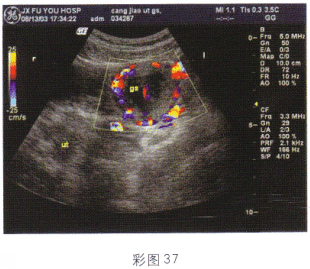

3.根据超声图像所示(彩图35),最可能的诊断是

A.附睾炎

B.睾丸扭转

C.卵巢囊肿蒂扭转

D.子宫腺肌病

E.附睾精液囊肿

正确答案:A解题思路:附睾肿大,可见低回声光团,形态不规则。